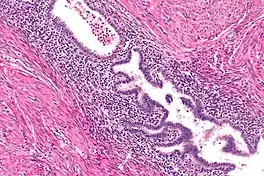

Gallbladder adenomyomatosis is a benign disease of the gallbladder characterized by hyperplasia of the mucosal epithelium and smooth muscle cells inside the muscularis propria.[4][5][6] The excessive proliferation of epithelial cells causes the mucosa to invaginate into the muscular layer lining the gallbladder wall, resulting in characteristic diverticula known as Rokitansky-Aschoff sinuses. These sinuses may be filled with biliary sludge, cholesterol crystals, or gallstones.[4][5][6]

Ultrasound is the preferred initial diagnostic choice for suspected gallbladder disease. Several distinct features of adenomyomatosis are discernable using ultrasound, making it a reliable modality for diagnosis.[4][5][6] The most characteristic features seen on ultrasound are the Rokitansky-Aschoff sinuses, which present either as echogenic foci when filled with biliary sludge/gallstones or anechogenic foci when filled with normal bile.[4][5][6] Other key features that may be seen include wall thickening and ring-down artifacts known as "comet tails" (produced by reverberations of sound between the sinuses).[4][5][6] Ultrasound can also distinguish between diffuse, segmental, and localized variants of adenomyomatosis based on morphology.[5][6]

In some cases, gallbladder wall thickening may be seen on ultrasound but is poorly defined and lacking specificity, particularly if the characteristic Rokitansky-Aschoff sinuses are not visualized. This can make it difficult to distinguish adenomyomatosis from other conditions that result in gallbladder wall thickening such as gallbladder cancer.[4][5][6] In these cases, MRI can prove helpful in providing the resolution needed for diagnosis. Especially effective is the T2-weighted MRI at visualizing the pathognomonic Rokitansky-Aschoff sinuses, which appear as round-shaped hyperintense cystic spaces that align in a curvilinear fashion along the gallbladder wall in a pattern described as the ”pearl necklace sign”.[4][5][6]